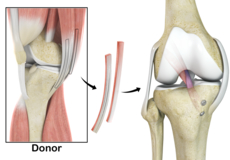

Hamstring Allograft

An allograft is an organ or tissue such as bone, cartilage, tendon or skin, taken from one person (donor) and surgically placed in another person to repair damaged tissue.